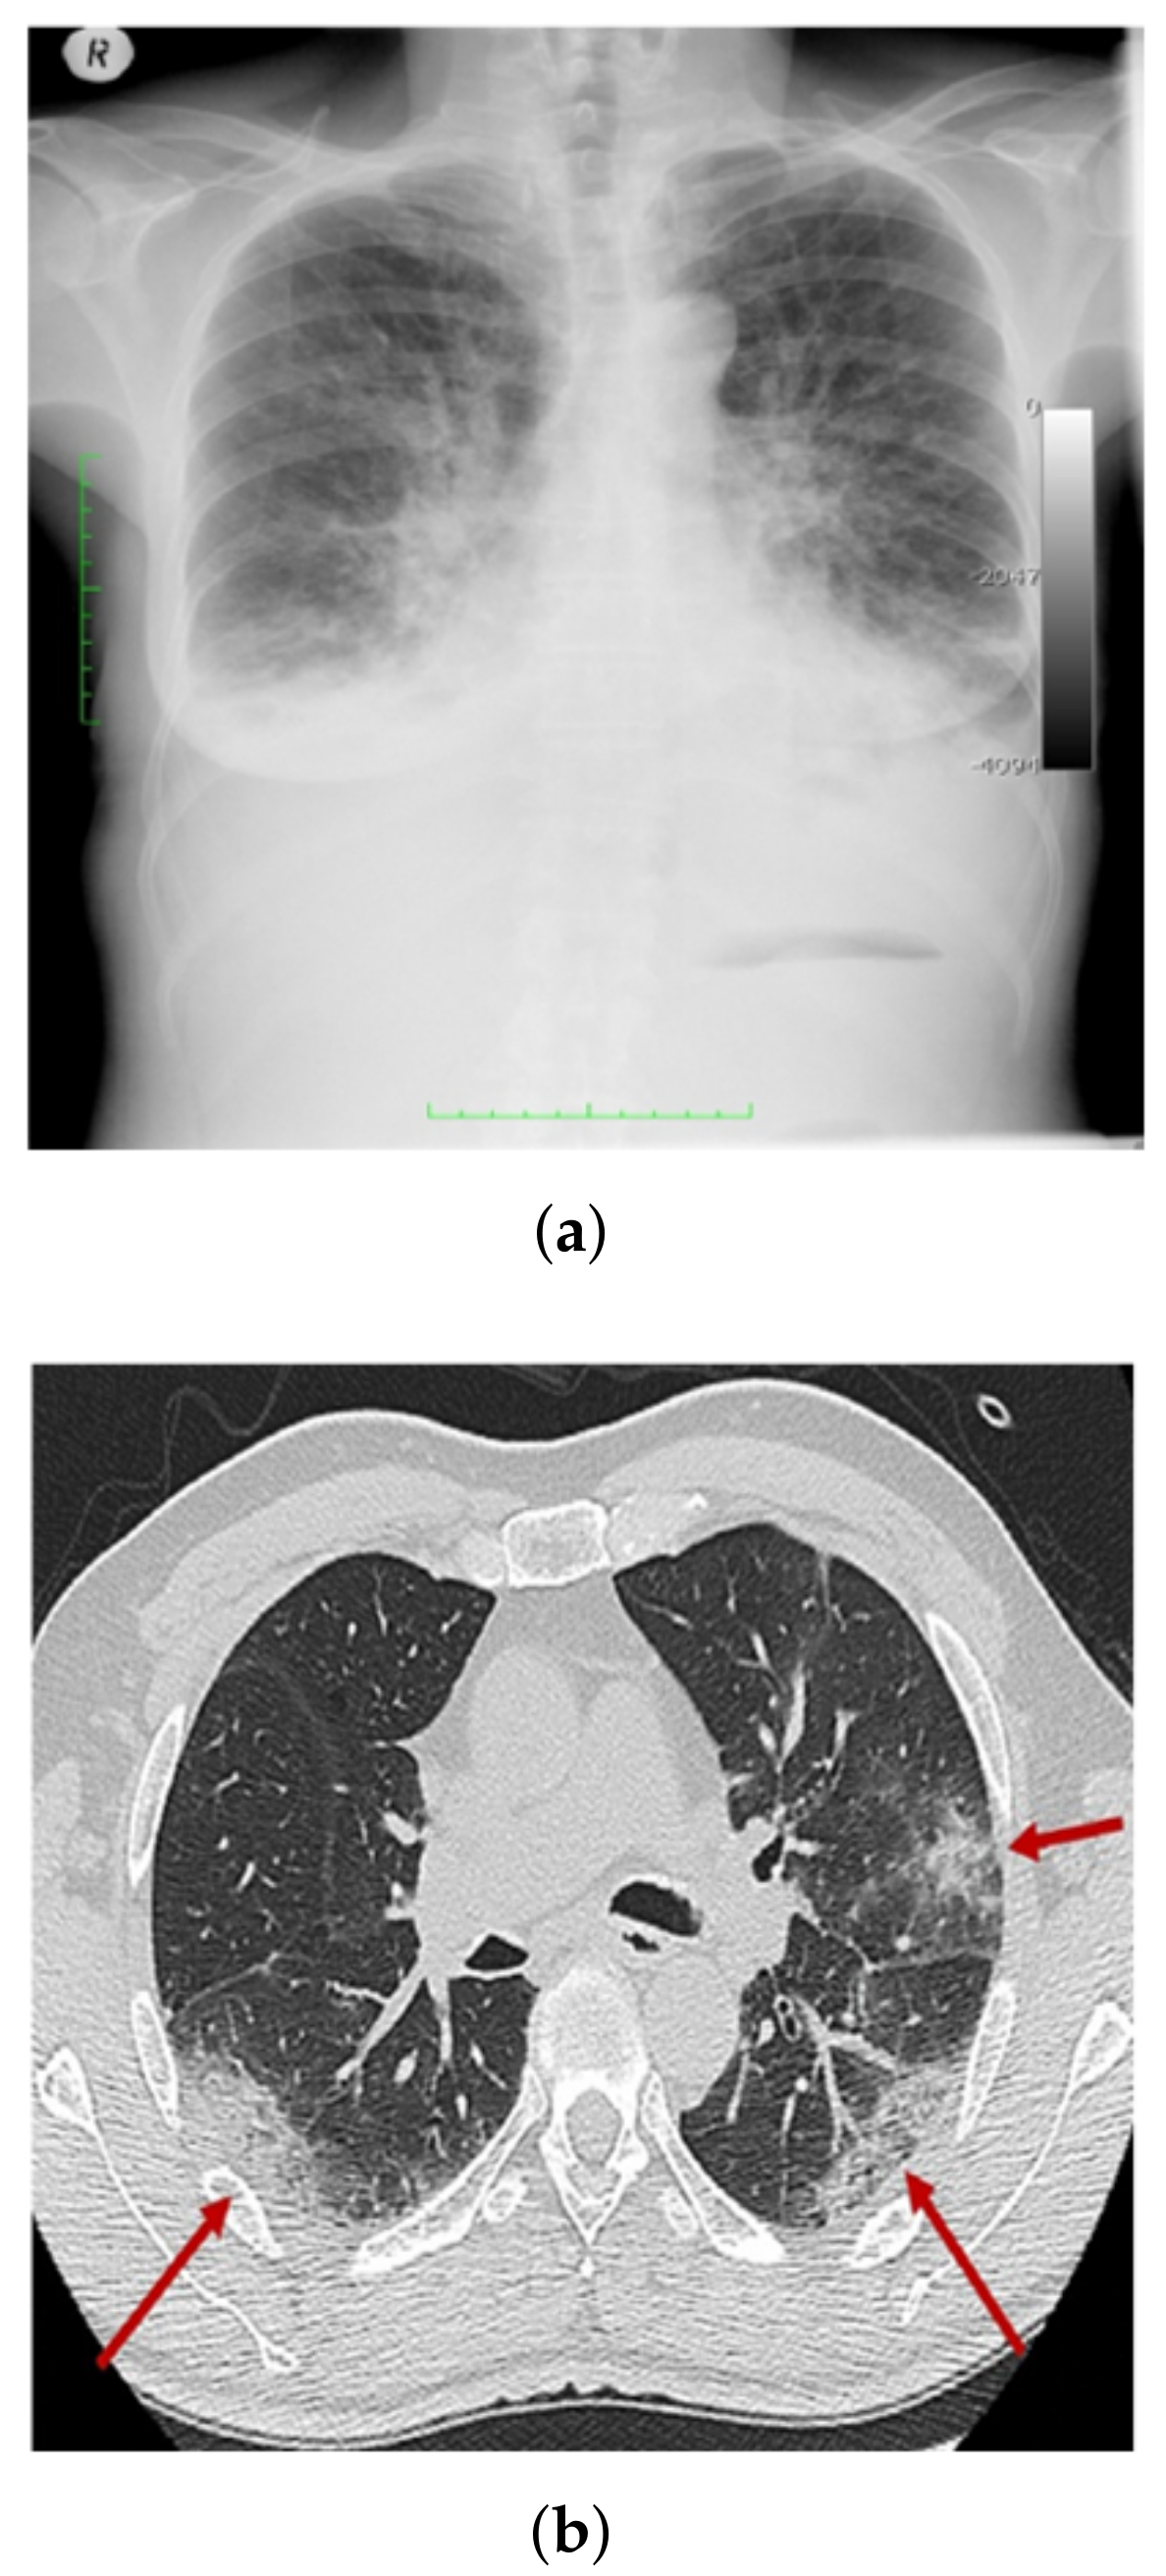

3.1. COV-PEN Image Datasets

3.2. Image Preprocessing Step